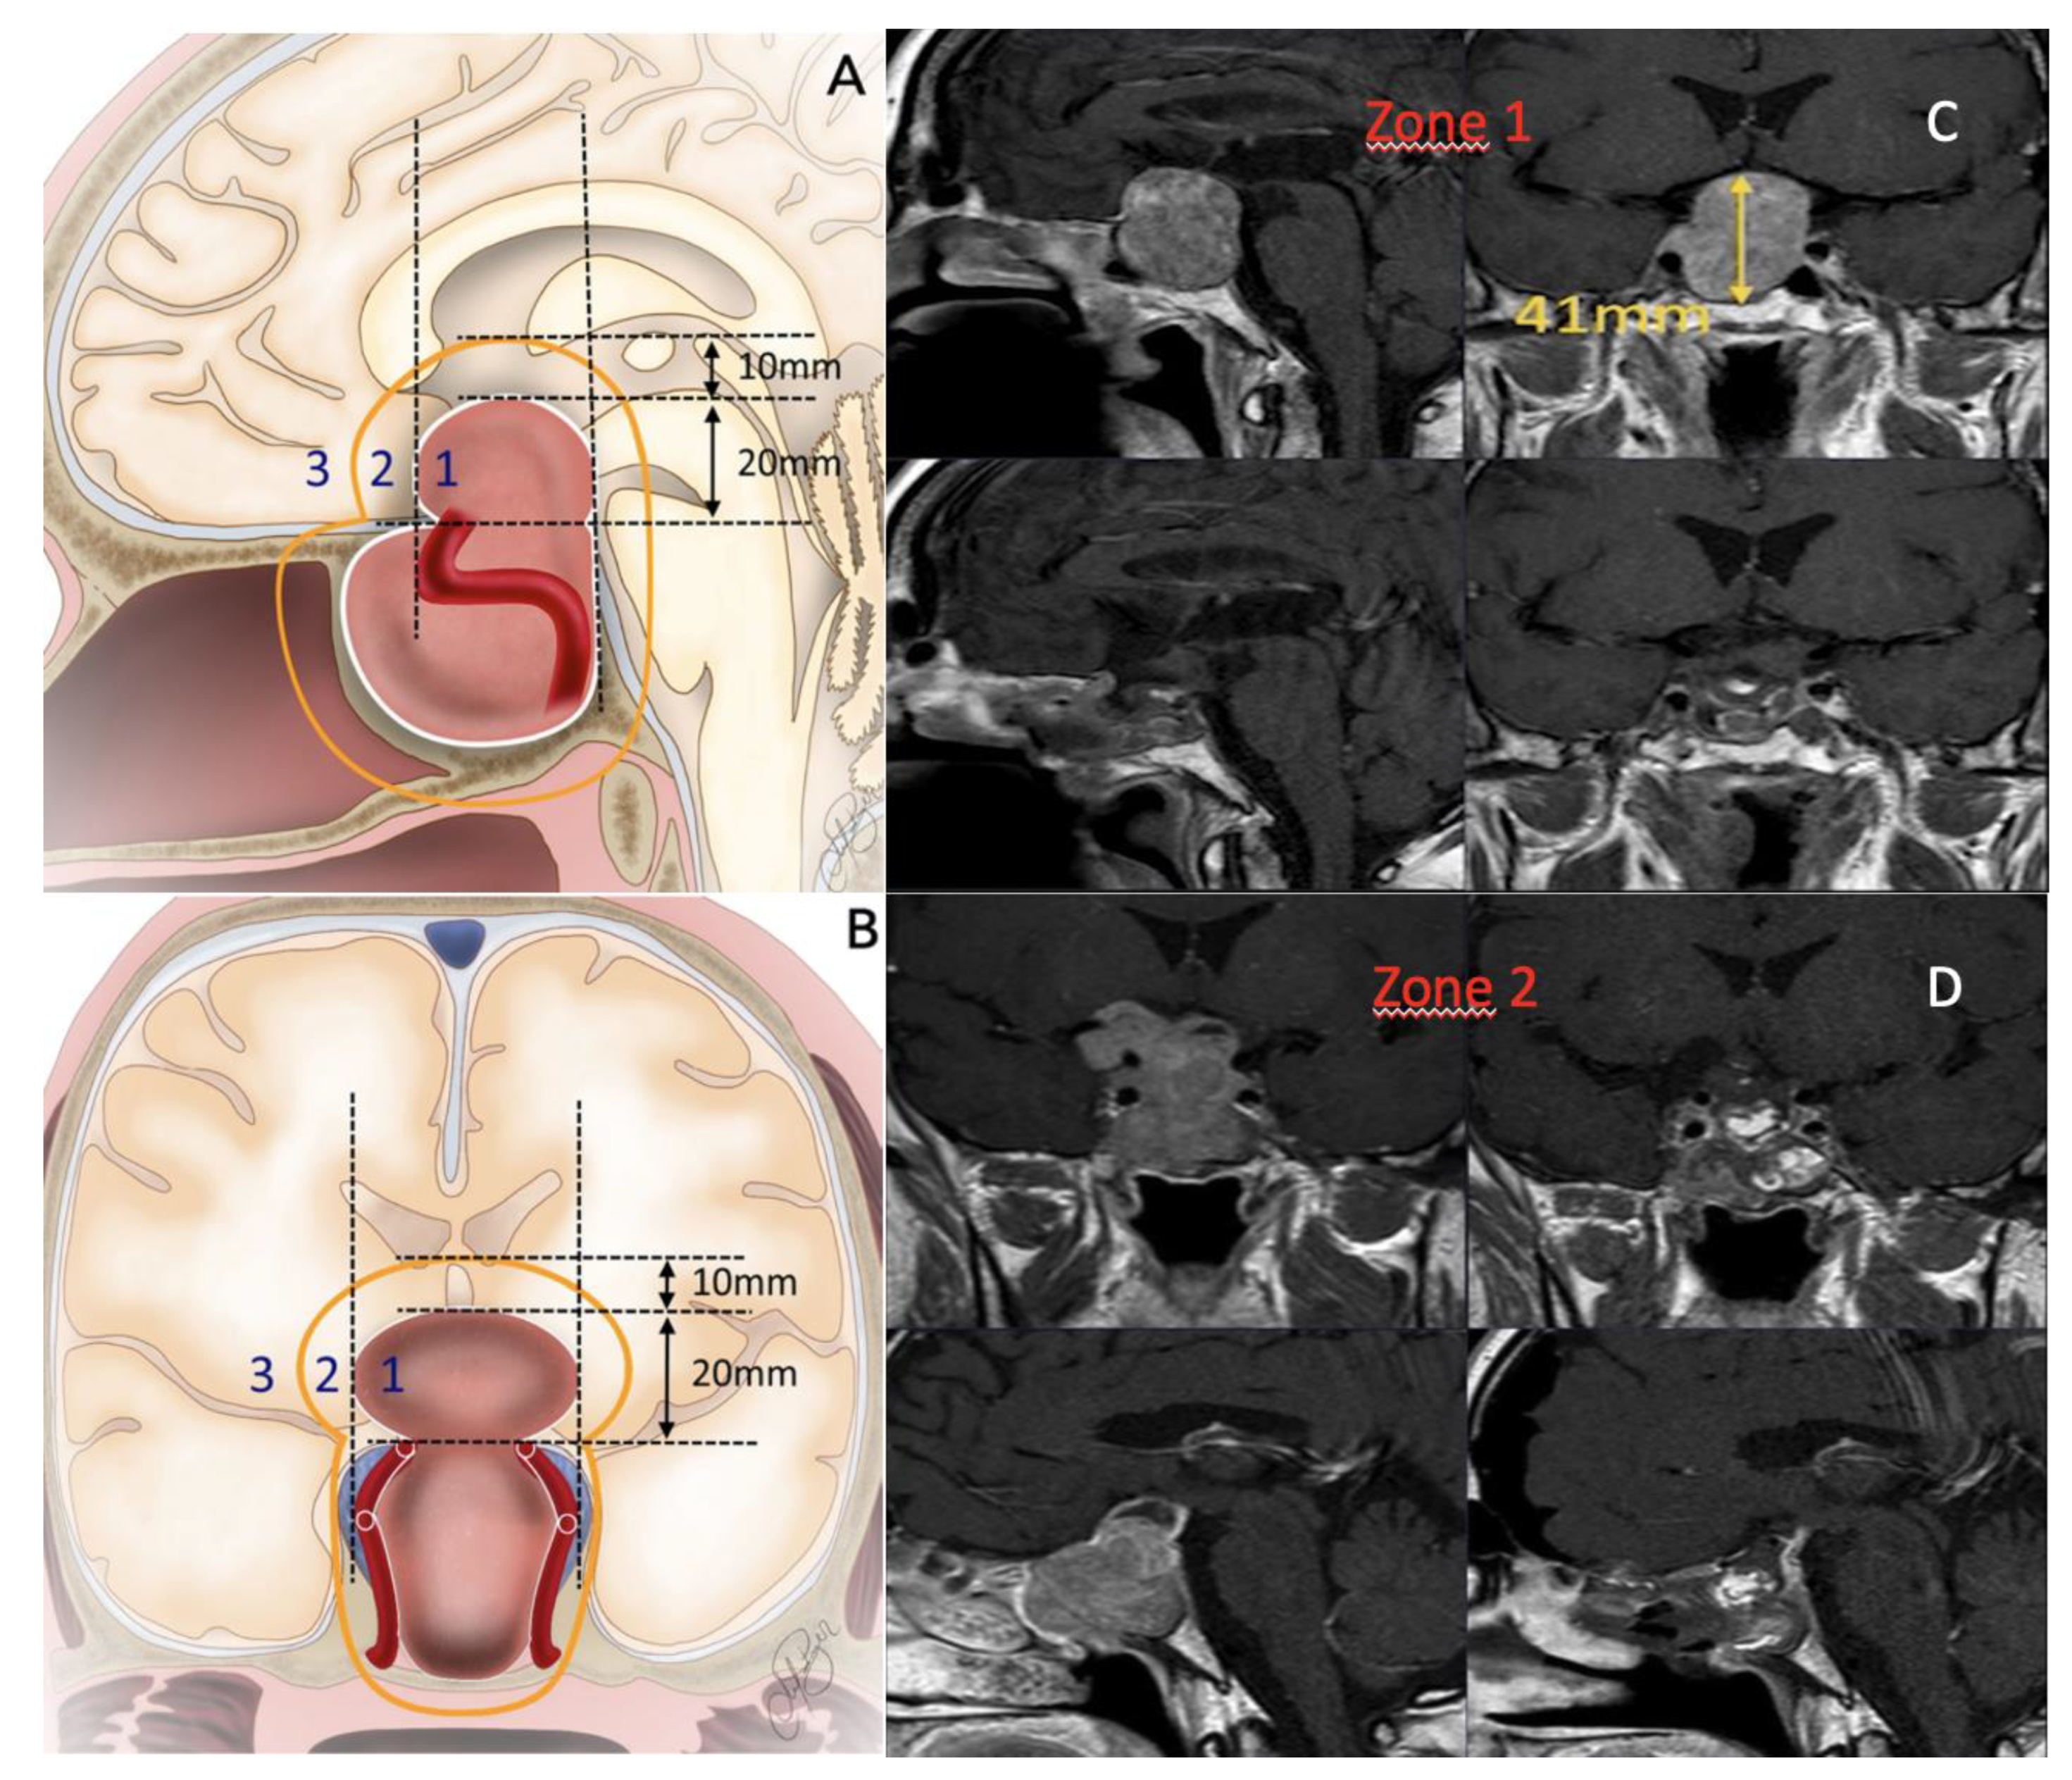

Tumor volume was categorized into Zone 1, Zone 2, and Zone 3 based on the “landmark-based classification” previously defined in our study[17].(Figure 1) This classification system enabled a standardized assessment of the tumor location and its spatial relationship with critical anatomical structures, providing a more objective evaluation of surgical strategy and resection outcomes. Complex cases were defined as tumors with Knosp grade 3/4 invasion or those located in Zone 3. The first postoperative MRI was performed within 24 h of surgery, with a follow-up MRI assessment conducted three months later. The extent of resection was determined based on the MRI performed within 24 h of surgery.

Figure 1. A. Landmark-Based Classification Sagittal Plane View B. Landmark-Based Classification Coronal Plane View C. Zone 1 Tumor: Preoperative and Postoperative NTR Imaging D. Zone 2 Tumor: Preoperative and Postoperative GTR Imaging.